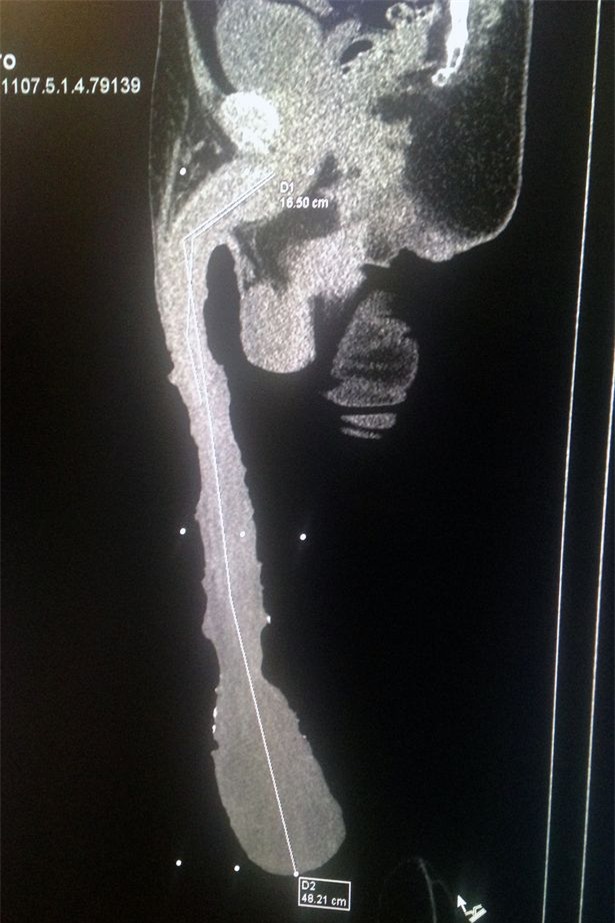

Theo Mirror, Roberto Esquivel Cabrera, 54 tuổi, có “của quý” dài tới 48cm. Ông nổi tiếng từ năm 2015.

“Của quý” dài gần nửa mét của ông đã đánh bại kỉ lục trước đó của diễn viên người Mỹ Jonah Falcon, người có “của quý” dài 23 cm.

Dương vật khổng lồ gây ra rất nhiều vấn đề sức khỏe cho Roberto cũng như khiến ông không thể có đời sống tình dục như người bình thường.